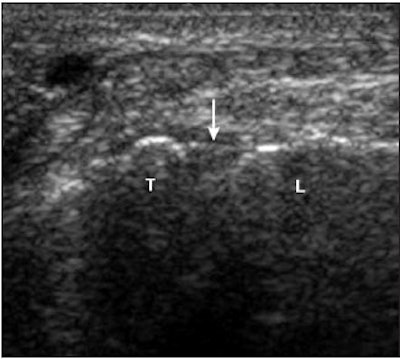

| Torn LTL. Above, transverse sonogram shows the dorsal aspects of the triquetrum (T) and lunate (L). The LTL fibers are not seen (arrow), which is consistent with a tear. Below, the LTL is not visualized on sonoarthrography (arrow) in the same patient. Note hypoechoic fluid extending between the triquetrum and lunate through the LTL tear. Intra-articular contrast improved visualization of the LTL tear. |